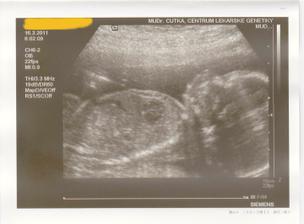

16.3.2011 - 3D ultrazvuk - genetické centrum - vše je OK